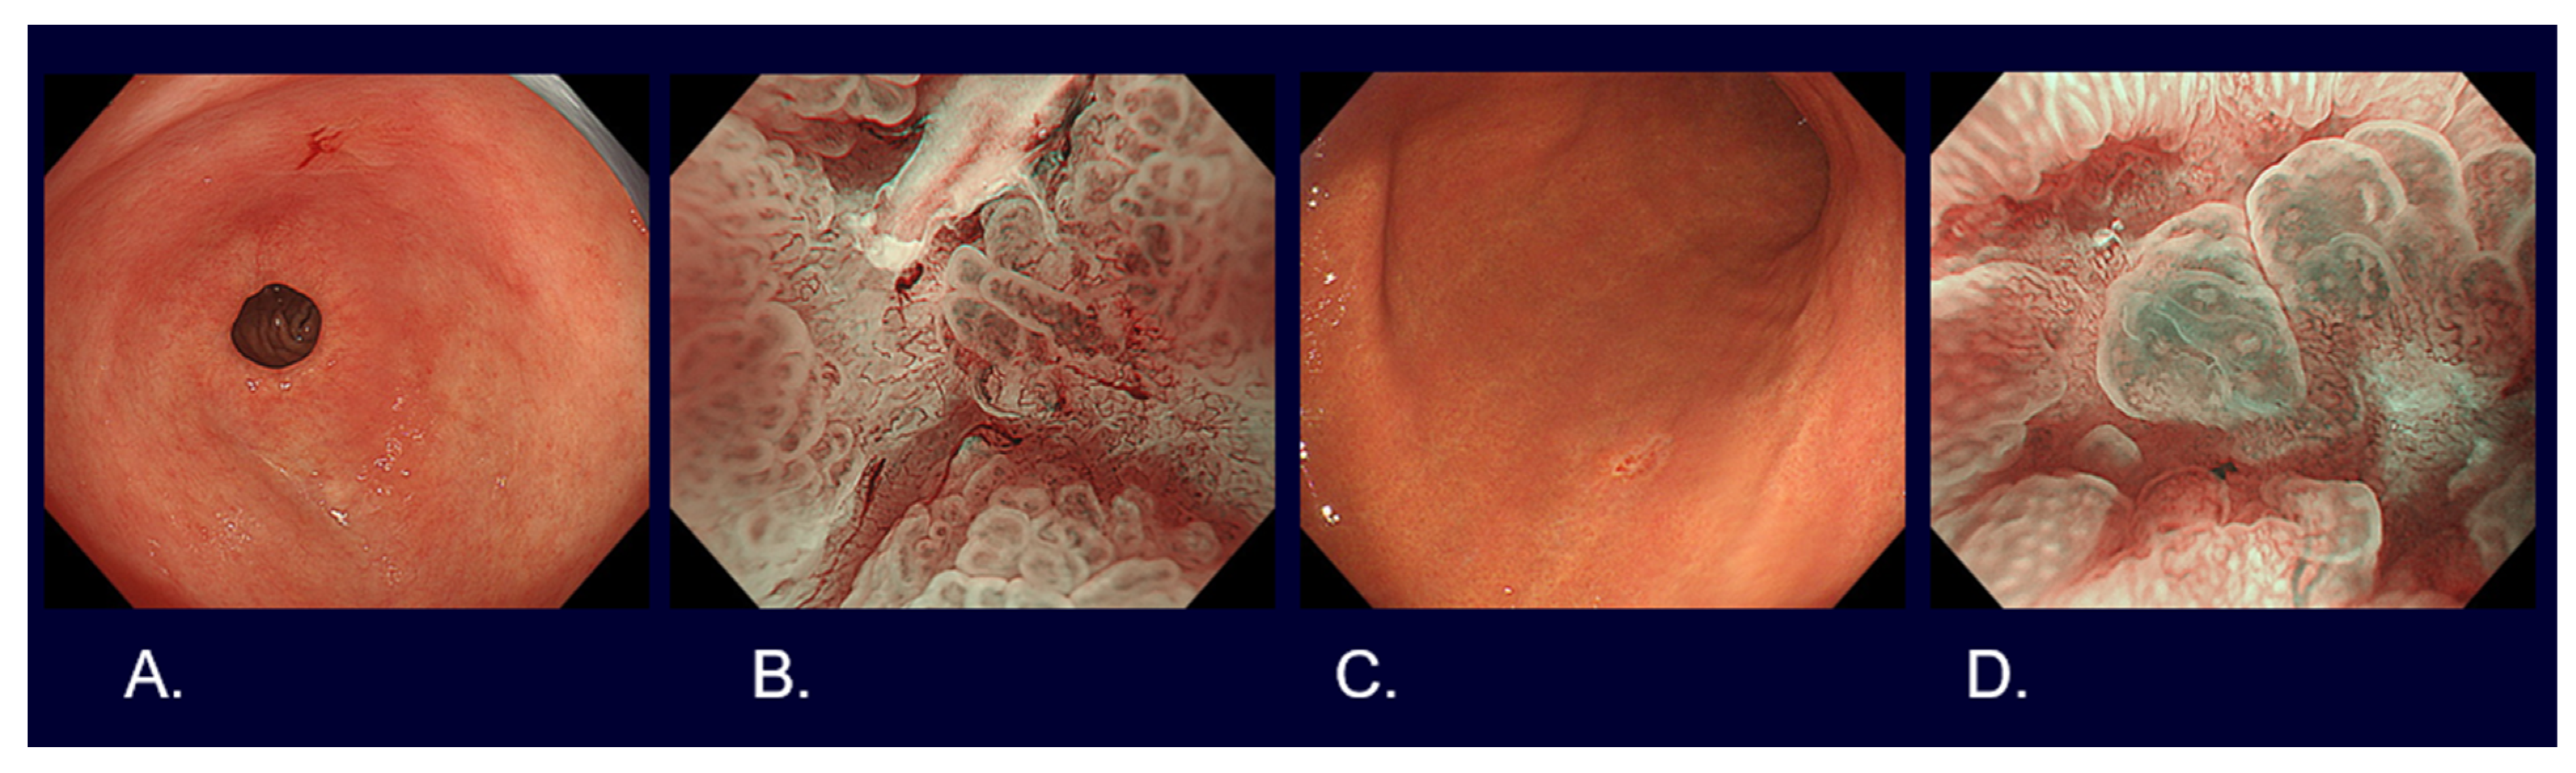

Flat and depressed cancers, which are characterized as areas with irregularities (a stellate shape) and a reddish or whitish color, are usually picked up by white light observation. Although it is often difficult to distinguish between cancer and non-cancer, new technologies are helping to overcome such difficulties. Detailed observation using magnifying endoscopy with band-limited light, such as narrow-band imaging (NBI), reveals an irregular microsurface and/or an irregular microvascular pattern with demarcation lines in the case of cancerous lesions (Figure 2). This new algorithm is known as the magnifying endoscopy simple diagnostic algorithm for gastric cancer (MESDA-G) [12], and it is based on the vessels plus surface (VS) classification system [13]. Although the progress of endoscopic diagnostic technology has been remarkable as described above, histological diagnosis with biopsy has to be conducted to confirm whether a lesion is cancer.

Figure 2. Endoscopic images of early gastric cancers. (A) White light observation of type 0-IIc differentiated cT1a without ulcerative findings, <2 cm in size, on the lesser curve of the gastric antrum. (B) Narrow-band imaging observation with 80 times magnification of Figure 1A lesion (irregular microvascular pattern with demarcation line). (C) White light observation of type 0-IIc undifferentiated cT1a without ulcerative findings, <2 cm in size, on the greater curve of the gastric body. (D) Narrow-band imaging observation with 80 times magnification of Figure 1C lesion (irregular microvascular pattern with demarcation line).